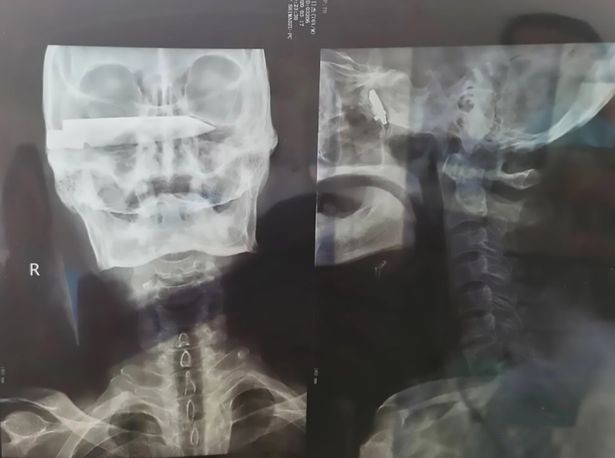

Người đàn ông 76 tuổi ở Trung Quốc bị cướp tấn công bằng dao vào những năm 1990 và một lưỡi dao dài 10cm không may đã găm vào hộp sọ dưới hốc mắt của ông.

Sau khi hội chẩn, nhóm chuyên gia quyết định thực hiện ca phẫu thuật làm 2 đợt. Trong ca phẫu thuật kéo dài 2 giờ vào ngày 2/4, họ đã lấy thành công lưỡi dao ra khỏi hộp sọ của bệnh nhân. Đến ngày 8/4, bệnh nhân trải qua ca phẫu thuật thứ 2 để làm sạch vết thương.